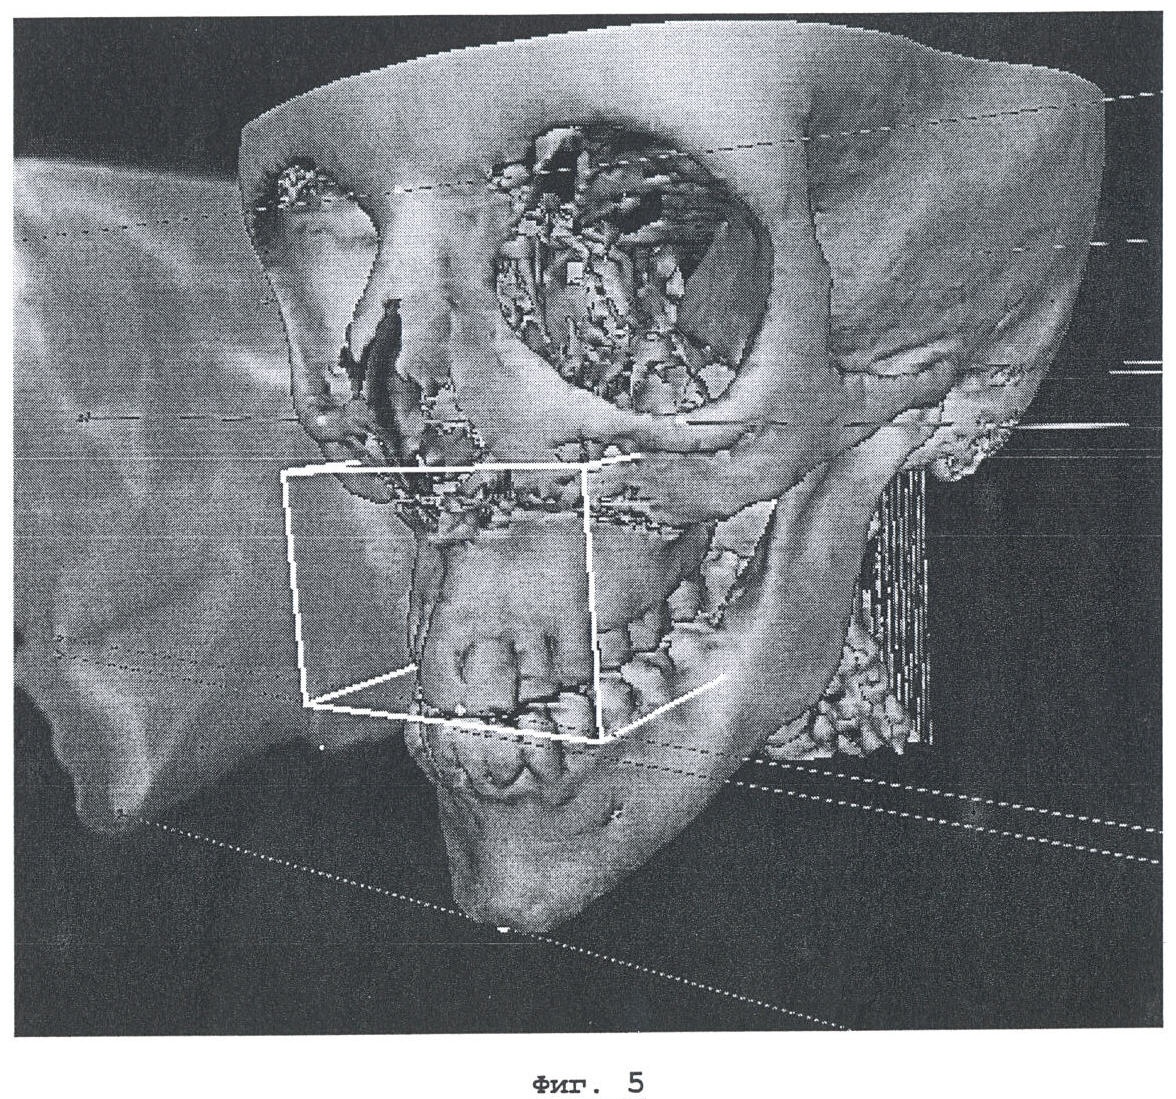

На фиг.5 показаны смещающиеся костные фрагменты в процессе подготовки к ортогнатической хирургии.

При подготовке к репозиции костного фрагмента можно получить дополнительную полезную информацию с помощью описанного выше трехмерного цефалометрического анализа (фиг.5). Имея такую информацию, пользователь (как правило, хирург) может виртуально осуществлять репозицию костных фрагментов. В качестве примера на фиг.6 приведен результат виртуальной репозиции верхней челюсти. Возможно моделирование различных типов поступательного перемещения и поворота относительно ориентиров с использованием компьютеризованной системы планирования. Так, например, поворот вокруг некоторой оси или поступательное перемещение вдоль некоторого направления могут быть определены как пересечение двух плоскостей или как перпендикулярные к некоторой плоскости, либо могут быть заданы двумя ориентирами.